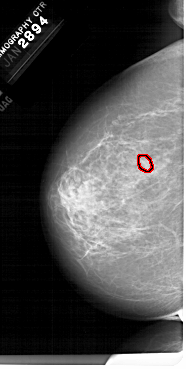

FILE: A_1679_1.LEFT_CC.OVERLAY

TOTAL_ABNORMALITIES 1

ABNORMALITY 1

LESION_TYPE MASS SHAPE LOBULATED MARGINS OBSCURED-CIRCUMSCRIBED

ASSESSMENT 4

SUBTLETY 3

PATHOLOGY BENIGN

TOTAL_OUTLINES 1

BOUNDARY